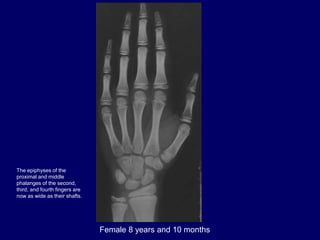

Female 8 years and 10 months

The epiphyses of the

proximal and middle

phalanges of the second,

third, and fourth fingers are

now as wide as their shafts.